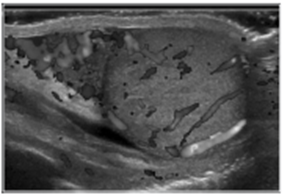

1) Testicular torsion: spermatic cord가 꼬임으로 말미암아 testis venous plexus의 폐색이 발생하고 이로 인해 testis의 울혈이 발생하여 결과적으로 arterial blood flow의 감소가 발생하게 되어 나타나게 되는 일련의 증상이다. 모든 소아환자의 25-30% 정도를 차지. 사춘기 acute scrotum의 경우 50-60%에서 해당. 이학적 검사상 거상된 고환이 관찰되고 cremasteric reflex가 나타나지 않으며 Prehn’s sign (ER note 참조)에서 음성소견이 관찰. Color doppler US에서 고환내 혈류가 없는 것으로 확진

좌측 그림은 좌측 고환의 혈류가 보이지 않음을 나타내고, 가운데 그림은 좌측 고환이 초막내 꼬여있음을 나타내는 영상임. 우측 그림에서 보듯, 수술 중 좌측 고환의 꼬임이 명확히 보이고 있으며, 정상에 비해 색변화가 뚜렷히 나타난다.